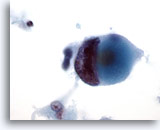

Figure 30

Breast FNA, Ductal carcinoma.

This low-power field shows abundant cellular necrosis with a tight cluster of cells in the center from a case of invasive ductal carcinoma. 20x

Figure 30

Breast FNA, Ductal carcinoma.

This low-power field shows abundant cellular necrosis with a tight cluster of cells in the center from a case of invasive ductal carcinoma.

20x